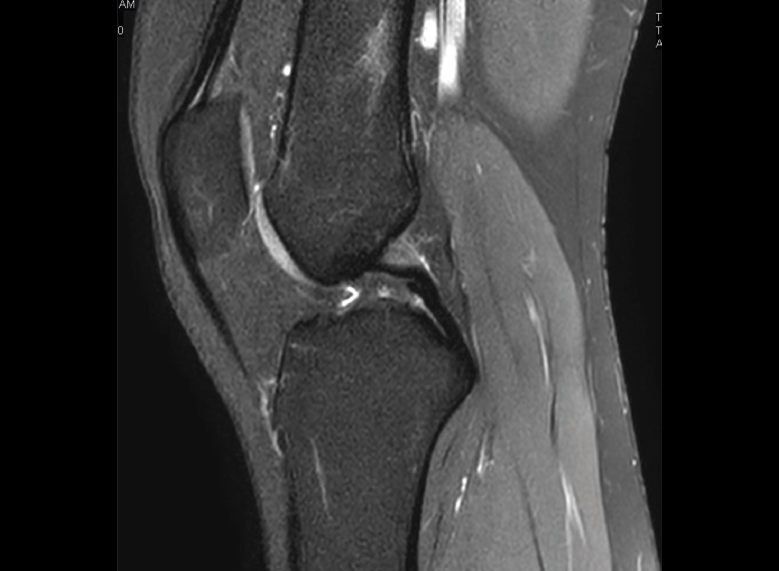

Resonancia magnética

Se basa en la propiedad que poseen los núcleos de hidrógeno de absorber energía electromagnética cuando están sometidos a un campo magnético intenso. La RM representa un mapa de la densidad de protones, o sea, de la distribución de agua por el organismo(12).

Se consiguen unas imágenes de alta resolución para la valoración de meniscos, ligamentos y tendones. Además, es especialmente útil en las rodillas operadas, lesiones tumorales, evaluación del cartílago y la visualización de los nervios(13).

1. Estudio de las estructuras intraarticulares

Es la prueba no invasiva de elección para valorar las lesiones internas de la rodilla(2). Aunque el estudio por RM es a menudo considerado como la prueba diagnóstica de elección para la detección de alteraciones meniscales, se asocia en ocasiones con errores diagnósticos(16).

1.1. Meniscos

Figura 30. Corte de secuencia sagital T2 Fat-Sat de resonancia magnética de rodilla: menisco externo normal.

Se identifican como estructuras hipointensas en todas las secuencias, con asta anterior y posterior de morfología triangular.

Figura 31. Corte de secuencia sagital T2 Fat-Sat de resonancia magnética de rodilla: menisco interno normal.

La RM es la técnica de elección en el diagnóstico de la patología meniscal(17)(Figuras 30, 31, 32, 33, 34 y 35).